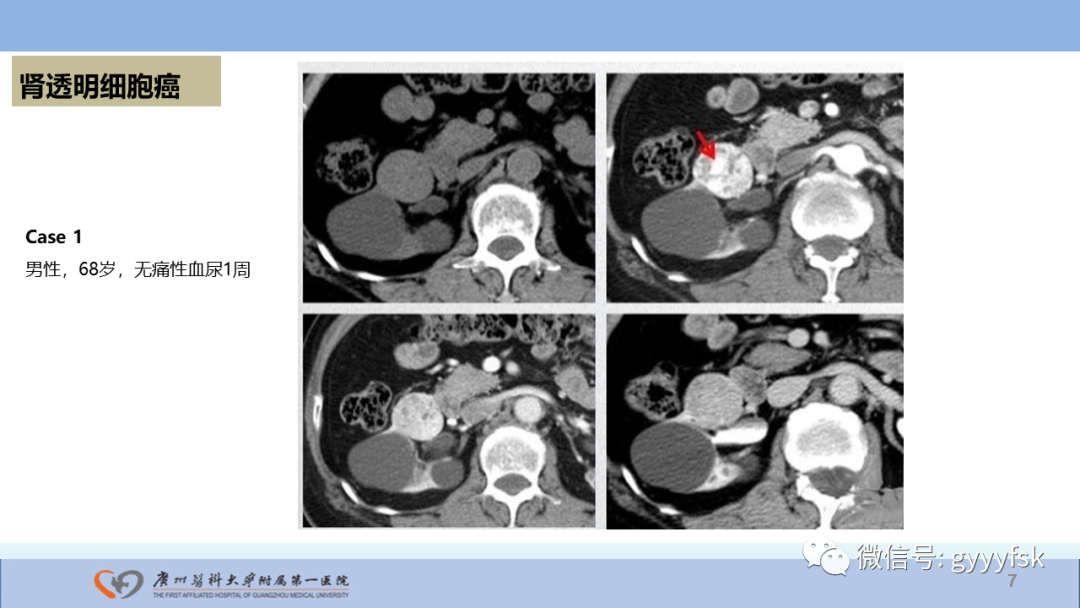

【PPT】肾癌相关影像诊断的文献汇报-7